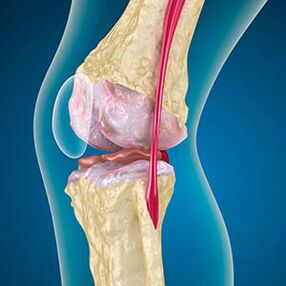

S artrózou je chrupavka lemující okraje kostí otěr nebo zcela nepřítomná. Poškozená tkáň není zdrojem bolesti, protože nemá receptory. Zánět v blízkých strukturách způsobuje charakteristické příznaky.

Tělo pokračuje v regeneraci poškozených tkání, ale chrupavka roste nerovnoměrně. Výsledkem je, že se vytvářejí nesrovnalosti, které poškozují jiné prvky kloubu. Povaha osteofytů je vysvětlena kompenzací hladké kloubní chrupavky. Jiná verze naznačuje, že růst „Spurs“ Je spojen s pokusem stabilizovat kloub mediálně nebo laterálně kvůli oslabení svalů.